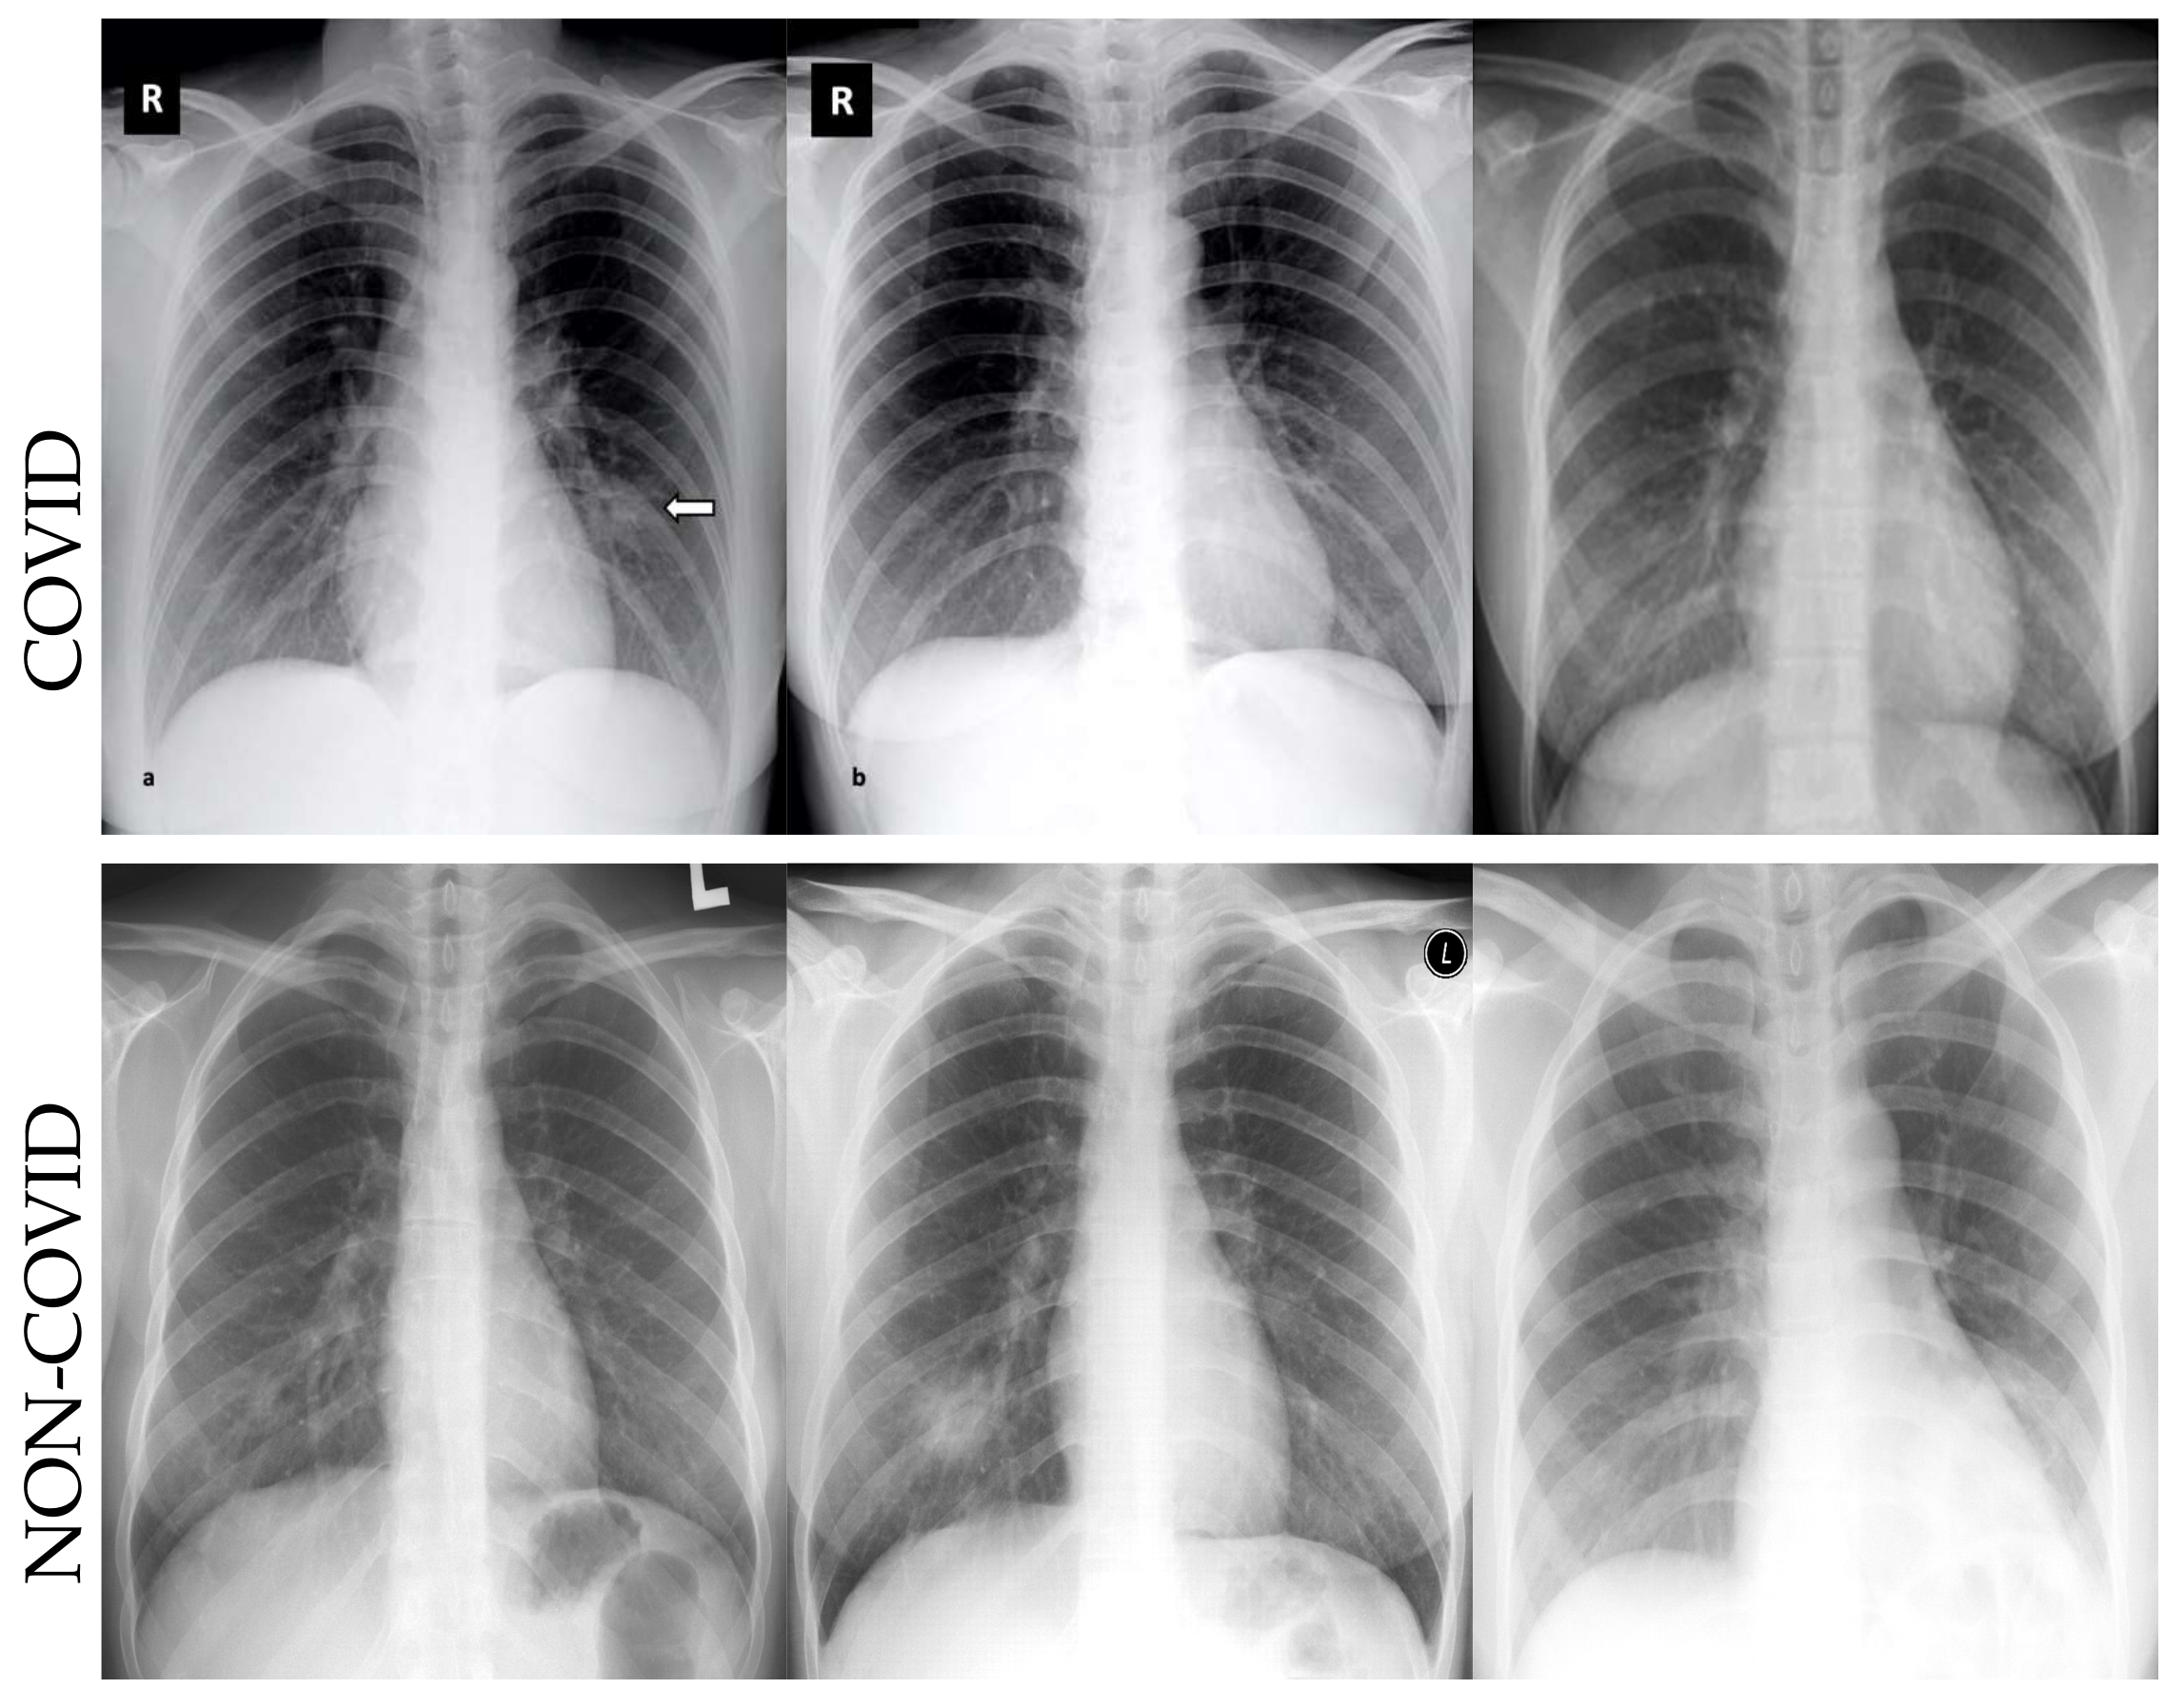

- We employ the deep learning algorithms for COVID-19 datasets to detect infection in the CT and X-ray images;

4.3. Metrics